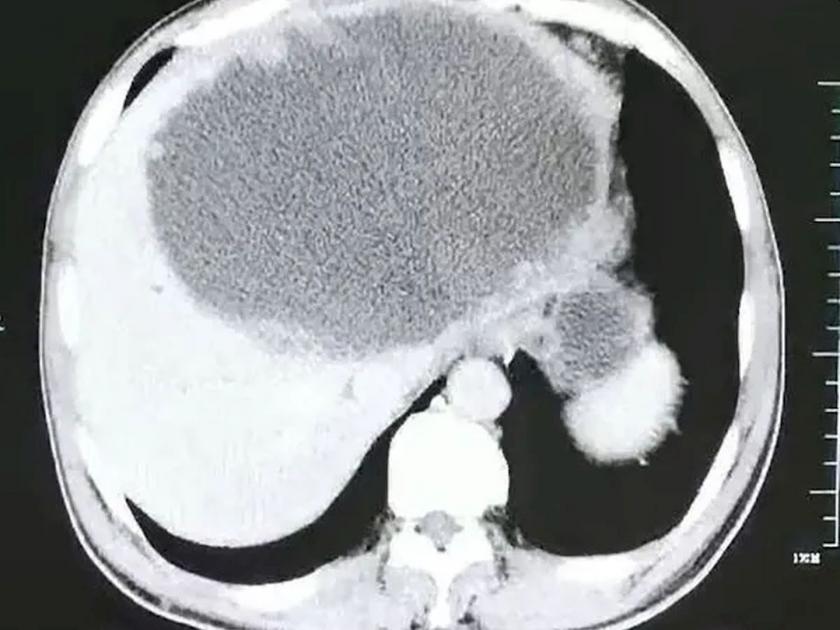

जवळपास ४ महिने रुग्णाला त्रास होत असल्यानं डॉक्टरांनी तातडीनं उपचार सुरू केले. त्यावेळी त्यांना रुग्णाच्या यकृतात पू आढळून आला. धक्कादायक बाब म्हणजे यकृतात १९ सेंटिमीटर लांब आणि १८ सेंटिमीटर रुंद भागात पू पसरला होता. याशिवाय या भागात गाठीदेखील तयार होऊ लागल्या होत्या. यानंतर विविध चाचण्या करण्यात आल्या. त्यामधून रुग्णाला क्लोनोरकिआसिस झाल्याचं निष्पन्न झालं. कृमींमुळे हा आजार होतो.

रुग्णाचं यकृत वाचवण्यासाठी डॉक्टरांनी त्यातील सर्व द्रव पदार्थ काढला. यानंतर डॉक्टरांनी यकृत कमी करण्याचा निर्णय घेतला. मात्र यकृतावरील गाठी तीन आठवड्यांनंतरही कायम राहिल्या. इतर कोणताही पर्याय नसल्यानं डॉक्टरांना यकृताचा बाधित भाग काढावा लागला. यामध्ये कृमींची अंडी आढळून आली. आपण अर्धवट शिजवलेला मासा खाल्ल्याची माहिती रुग्णानं डॉक्टरांना दिली. या माशाच्या पोटात असलेल्या कृमींनी रुग्णाच्या पोटात अंडी दिल्यानं हा संपूर्ण प्रकार घडल्याचं डॉक्टरांनी सांगितलं.